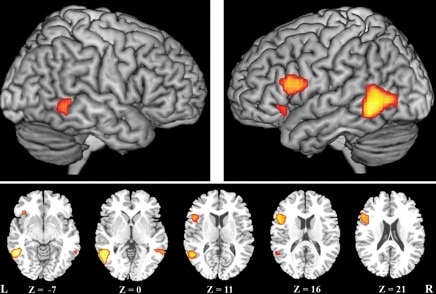

Η ομιλία παράγεται στο λάρυγγα, με τη λειτουργία διάφορων μυών (στο στόμα, στο φάρυγγα κλπ). Η εντολή για την παραγωγή του λόγου δίνεται στον εγκέφαλο, όχι σε ένα κέντρο όπως πιστευόταν παλιά, αλλά σε διάφορες περιοχές του εγκεφάλου, που συνεργάζονται μεταξύ τους.

Η δυσαρθρία μπορεί να οφείλεται σε μυοπάθεια, μυασθένεια, νευροπάθειες, νόσο του κινητικού νευρώνα, νόσο της παρεγκεφαλίδας, όγκους εγκεφάλου, αγγειακά εγκεφαλικά επεισόδια, νόσο του Πάρκινσον κλπ.